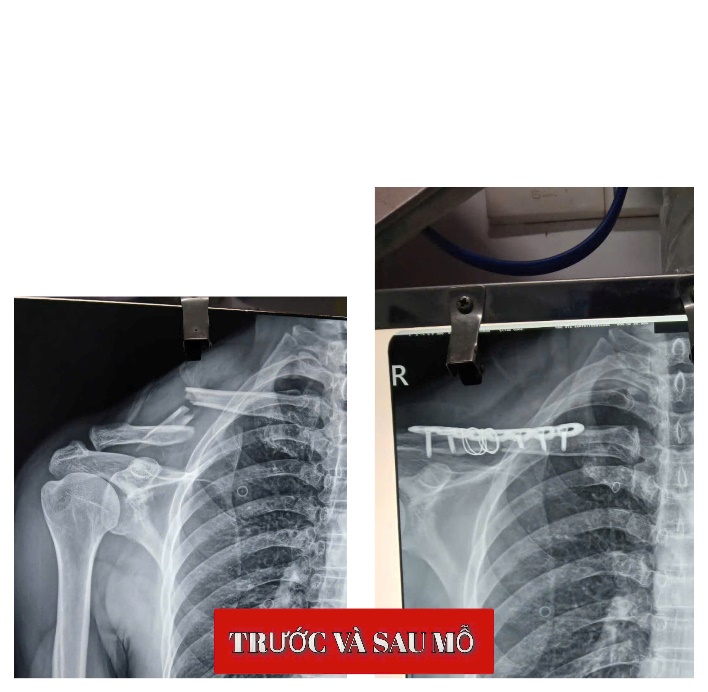

Nhiều trường hợp gãy xương lớn, phức tạp do tai nạn giao thông đã được phẫu thuật kết hợp xương và điều trị thành công tại bệnh viện. Nhờ sự quan tâm đầu tư của lãnh đạo bệnh viện trong lĩnh vực chấn thương chỉnh hình, từ nhân lực đến trang thiết bị máy móc, nhiều ca bệnh trước đây phải chuyển tuyến nay đã được xử trí hiệu quả ngay tại địa phương.

Hình 5. Các trường hợp gãy xương được phẫu thuật kết hợp xương.

BSCKI. Ngô Nhật Trường Khoa, chuyên khoa chấn thương chỉnh hình của Khoa Ngoại cho biết: “Trước đây, nhiều trường hợp gãy xương có chỉ định phẫu thuật buộc phải chuyển tuyến trên. Hiện nay, với sự đầu tư đồng bộ về chuyên môn và trang thiết bị, nhiều ca đã được điều trị thành công tại bệnh viện, giúp giảm tải tuyến trên và tạo thuận lợi cho người bệnh.”